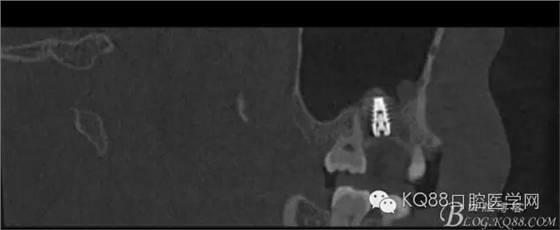

下面是拔牙后三個(gè)月的CBCT。垂直骨高度約6.7mm。

另外一個(gè)切面。垂直骨高度不夠,準(zhǔn)備 :做內(nèi)提升,植骨,植入植體。

植入后,CBCT

另外一個(gè)切面。竇底粘膜完整連續(xù)。可以看到上下咬合的位置關(guān)系。